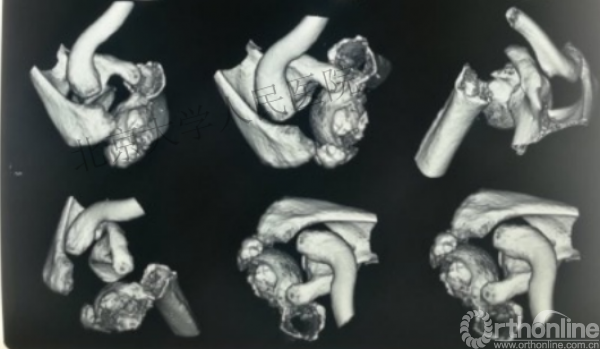

内侧皮质粉碎,低位外科颈骨折,肱骨头-干角维持困难。

术后复位丢失,肱骨头内翻畸形。

另一个留有遗憾的病例,您的选择?PHN?